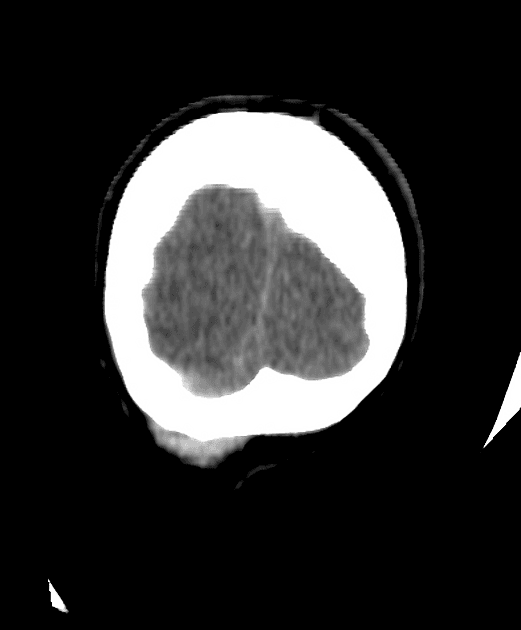

Axial ADC

MRI•Axial ADC•1 / 20

- Ghi nhận sự thay đổi tín hiệu (signal alteration) tại tiểu não (cerebellum), thùy chẩm (occipital lobes), nhân bèo (putamina), đầu nhân đuôi (caudate nuclei - head), trung tâm bán bầu dục (centrum semiovale), vành tia (corona radiata) hai bên và lồi chai thể (splenium of corpus callosum).

- Các vùng tổn thương biểu hiện tăng tín hiệu (hyperintensity) trên xung FLAIR và T2W, hạn chế khuếch tán (diffusion restriction) và giảm tín hiệu (hypointensity) trên xung T1W.

- Không phát hiện hình ảnh xuất huyết (no hemorrhage was detected).